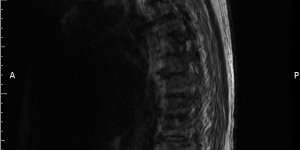

Back Pain | Ankylosing Spondylitis | Cases

Published on Jan 20, 2021

26 ♂ Presented to MSK service with back pain. Gave a 7 year history of back pain (started aged 19) Seen previously in MSK service 5 years ago (aged 21). Had an MRI scan which was normal. Has has physiotherapy in the past. Has been regularly having chiropractic treatment. Reports that his back remains arched when he is lying supine (lordosis [...] Read more